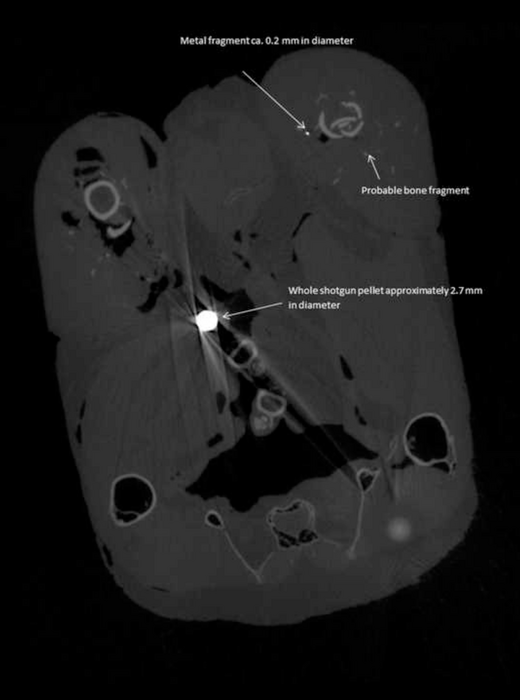

The researchers used a high-resolution CT (computerised tomography) scanner to locate the lead fragments in the pheasant meat in three dimensions, and measure their size and weight. The meat was then dissolved, allowing the larger fragments to be extracted and analysed further to confirm they were lead.

An average of 3.5 lead pellets and 39 lead fragments of less than 1mm wide were detected per pheasant. The smallest fragments were 0.07mm wide – at the limit of resolution for the CT scanner for specimens of this size - and the researchers say it is likely that even smaller fragments were also present.

The lead pieces were widely distributed within the birds’ tissues and some of the small fragments were over 50mm from the nearest lead shot pellet.